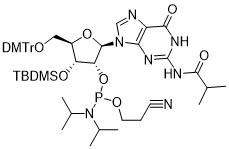

馬鞍山致研生物醫(yī)藥科技有限公司成立于馬鞍山市鄭浦港新區(qū)現(xiàn)代產(chǎn)業(yè)園。公司專(zhuān)注于生物小分子、醫(yī)藥中間體相關(guān)產(chǎn)品的研發(fā)和生產(chǎn),產(chǎn)品主要包括DNA亞磷酰胺單體、RNA亞磷酰胺單體、特殊單體以及按照客戶(hù)要求定制的RNA和DNA,并且公司提供定制合成等方面的研究服...

馬鞍山致研生物醫(yī)藥科技有限公司成立于馬鞍山市鄭浦港新區(qū)現(xiàn)代產(chǎn)業(yè)園。公司專(zhuān)注于生物小分子、醫(yī)藥中間體相關(guān)產(chǎn)品的研發(fā)和生產(chǎn),產(chǎn)品主要包括DNA亞磷酰胺單體、RNA亞磷酰胺單體、特殊單體以及按照客戶(hù)要求定制的RNA和DNA,并且公司提供定制合成等方面的研究服...